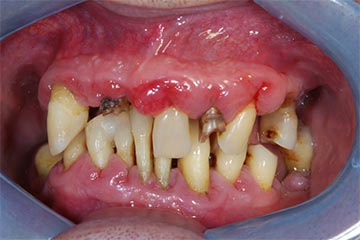

I denti irrecuperabili dell'arcata superiore ed inferiore del paziente di anni 65

sono stati sostituiti da 10 impianti, cioè protesi radicolari endo-ossee che sostengono le protesi fisse superiore ed inferiore.